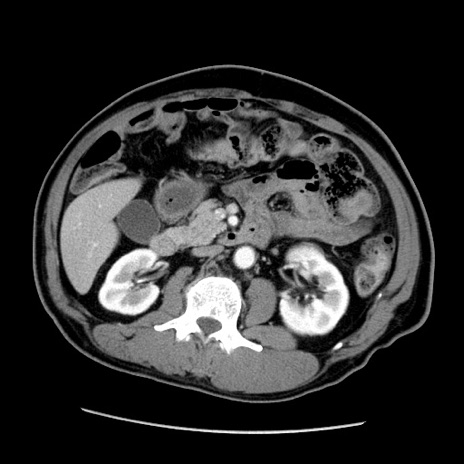

冠状断像

【症例】50歳代男性

【主訴】腹痛

【現病歴】AVMからの被殻出血のため回復期リハ病棟入院中。 本日午後3時頃急に下腹部痛が出現した。

【既往歴】AVM、被殻出血、虫垂炎、高血圧

【身体所見】意識晴明、左半身不全麻痺、会話の理解は良好、36.5°C、腹部:膨隆、全体に板状硬、下腹部正中に圧痛点あり、反跳痛-、筋性防御不明、右下腹部にope scar

【データ】WBC 9400、CRP 0.06